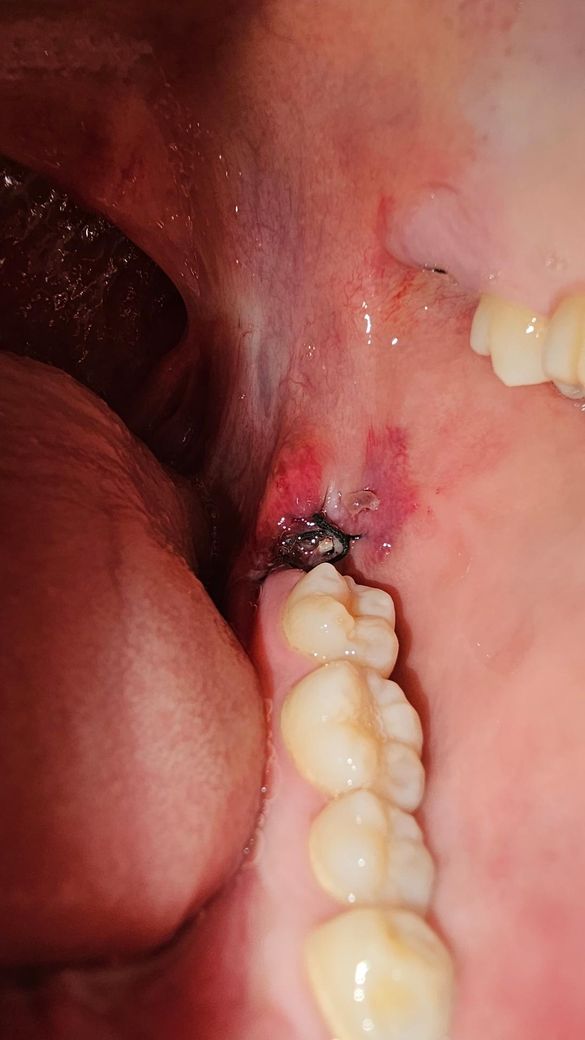

매복사랑니 발치 3일차인데 하얀색 점같은게있어요

안뇽하세요 매복사랑니 발치한지 3일차인데 아랫쪽에 뭔가 하얀색 점같은게 생겼는데 이거 음식물 찌거기인가요? 정상적으로 치유되고있는건가요?

• 3번 째 사진

사랑니를 발치하고 나면 발치한 부위에 가피등이 형성될수 잇습니다. 사진으로 봤을 경우에는 크게 문제가 없는것으로 보이기 때문에 너무 걱정하지 않으셔도 될것으로 생각됩니다.

2. 발치 부위의 하얀색 점처럼 생긴 것은 단순 이물질 같습니다. 살살 가글해서 위생관리 해주세요.

3. 치과에서 설명한 발치 후 주의사항 잘 지켜주세요